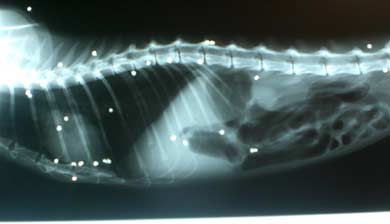

31 Kugeln im Körper!- Neurone geht

es sehr schlecht!

Neurones Allgemeinbefinden ist schlecht. Wir

hoffen er schafft es . Als der Kater untersucht

wurde, entdeckten die Tierärzte auf dem

Röntgenbild, dass Neurones Körper

mit Kugeln förmlich gespickt ist. So

viele Kugeln (bzw Teile) in einem Tier haben

sie bisher noch nicht gesehen.

Die Bluttests sind da, die Bleiwerte sind

momentan noch nicht bedenklich, dass heisst

sein momentan schlechter Zustand beruht nicht

hauptursächlich auf einer Bleivergiftung,

das ist ja schon mal was!

Allerdings besteht in Zukunft kaum die Möglichkeit

ihn von seinen Schrotkugelteilen zu befreien,

die sind zwar auf dem Röntgenbild super

zu sehen, aber man findet sie dann nicht leicht

in der Katze, dazu müsste man das ganze

Weichteil- und Muskelgewebe durchsuchen und

würde gar nicht alles finden.